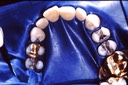

Ted Ramage Slides - Class III restorations on cuspids